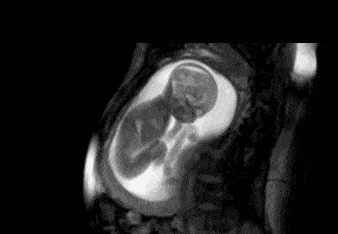

胎儿在母亲肚子里时位置是变化的,当胎儿头朝下或与母亲面对面时,腹部被挡住了,使用B超是检查不出来的。

B超检查的结果,也与超声医生的技术水平有关。专家建议,妊娠期间,每个准妈妈做3次超声波检查是很有必要的,因为目前B超依然是最及时和安全地发现问题的手段。

在专业的医疗机构,60%的胎儿先天缺陷可以在第12周和第22周的超声波检测中辨认出来,所以及时进行B超检查很有必要!